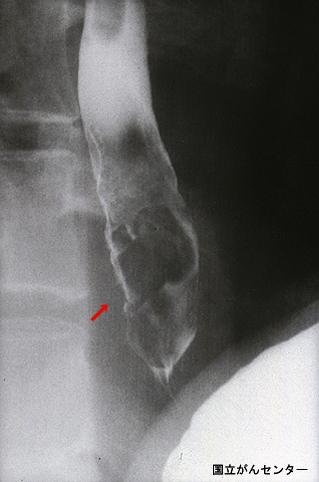

部位(按器官分)食道/下

检查方法X线

肿瘤的肉眼分类0型(表在型)/I型(Ipl)

肿瘤最大直径30~34

肿瘤的深度sm